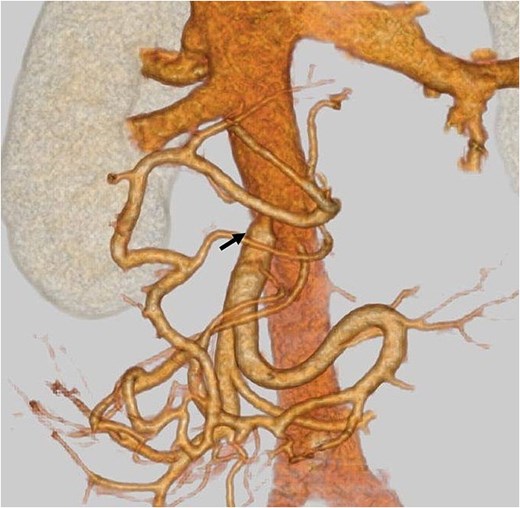

An elderly woman in her 80s presented to our hospital with prolonged epigastric pain. She was diagnosed with pancreatic cancer (PC) in the uncinate process, with severe stenosis of the SMV (Fig. 1a, left). She had previously undergone laparoscopic right hemicolectomy for cecal cancer 6 years earlier. The PC was considered borderline resectable without lymphadenopathy or evidence of distant metastasis, and she received three cycles of NAC with gemcitabine plus nab-paclitaxel (GnP). Although the SMV stenosis showed mild improvement after NAC (Fig. 1a, right), preoperative 3D imaging revealed that the jejunal veins drained separately and that prominent collateral pathways bypassing the SMV–PV axis had developed (Fig. 1b). We obtained fully informed consent, particularly regarding the potential procurement of a VG from her neck, and a pancreaticoduodenectomy was planned, preserving the collateral venous pathways and without SMV reconstruction.

(a) Preoperative contrast-enhanced CT in the portal venous phase demonstrated a hypovascular tumor measuring 20 mm in the pancreatic uncinate process and mild improvement in SMV narrowing (arrow, pre-NAC in left image, post-NAC in right image). (b) Preoperative 3D imaging demonstrated that the jejunal veins were discontinued separately, and there are three collateral pathways, via posterior superior pancreaticoduodenal vein, inferior mesenteric vein through the right gastroepiploic vein, and stenotic SMV with intramesenteric anastomoses. SMV: Superior mesenteric vein, NAC: Neoadjuvant chemotherapy.